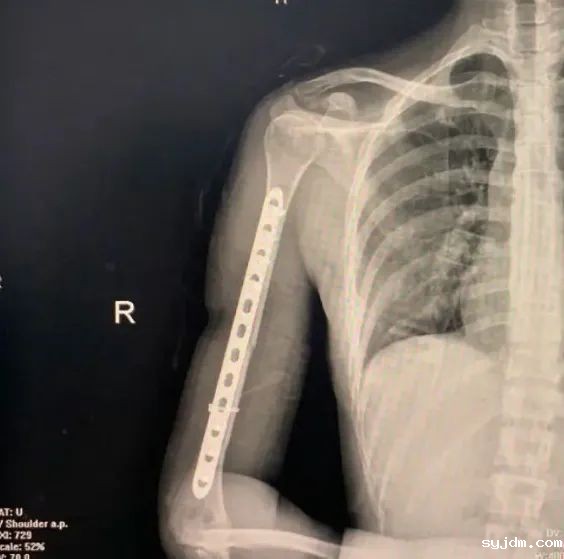

首先,先来看个经典案例。演员万茜在参加“乘风破浪的姐姐”节目期间,不幸遭遇车祸,导致右肱骨骨折。受伤后立即进行了骨折复位内固定手术。就在大家都以为万茜即将遗憾告别舞台时,却惊奇地发现,仅仅术后一周,万茜就重返舞台。受伤的右臂甚至可以抬起,完成一些简单的舞蹈动作.

如此令人惊叹的恢复速度,在网络上却引发了争议。有网友调侃出现了“医学奇迹”,怀疑万茜诈伤,恶意炒作博取同情。按理说,“伤筋动骨一百天”,这才十来天,就能如此“生龙活虎”?太不科学了。万茜如此快的康复速度,究竟是不是“医学奇迹”呢?